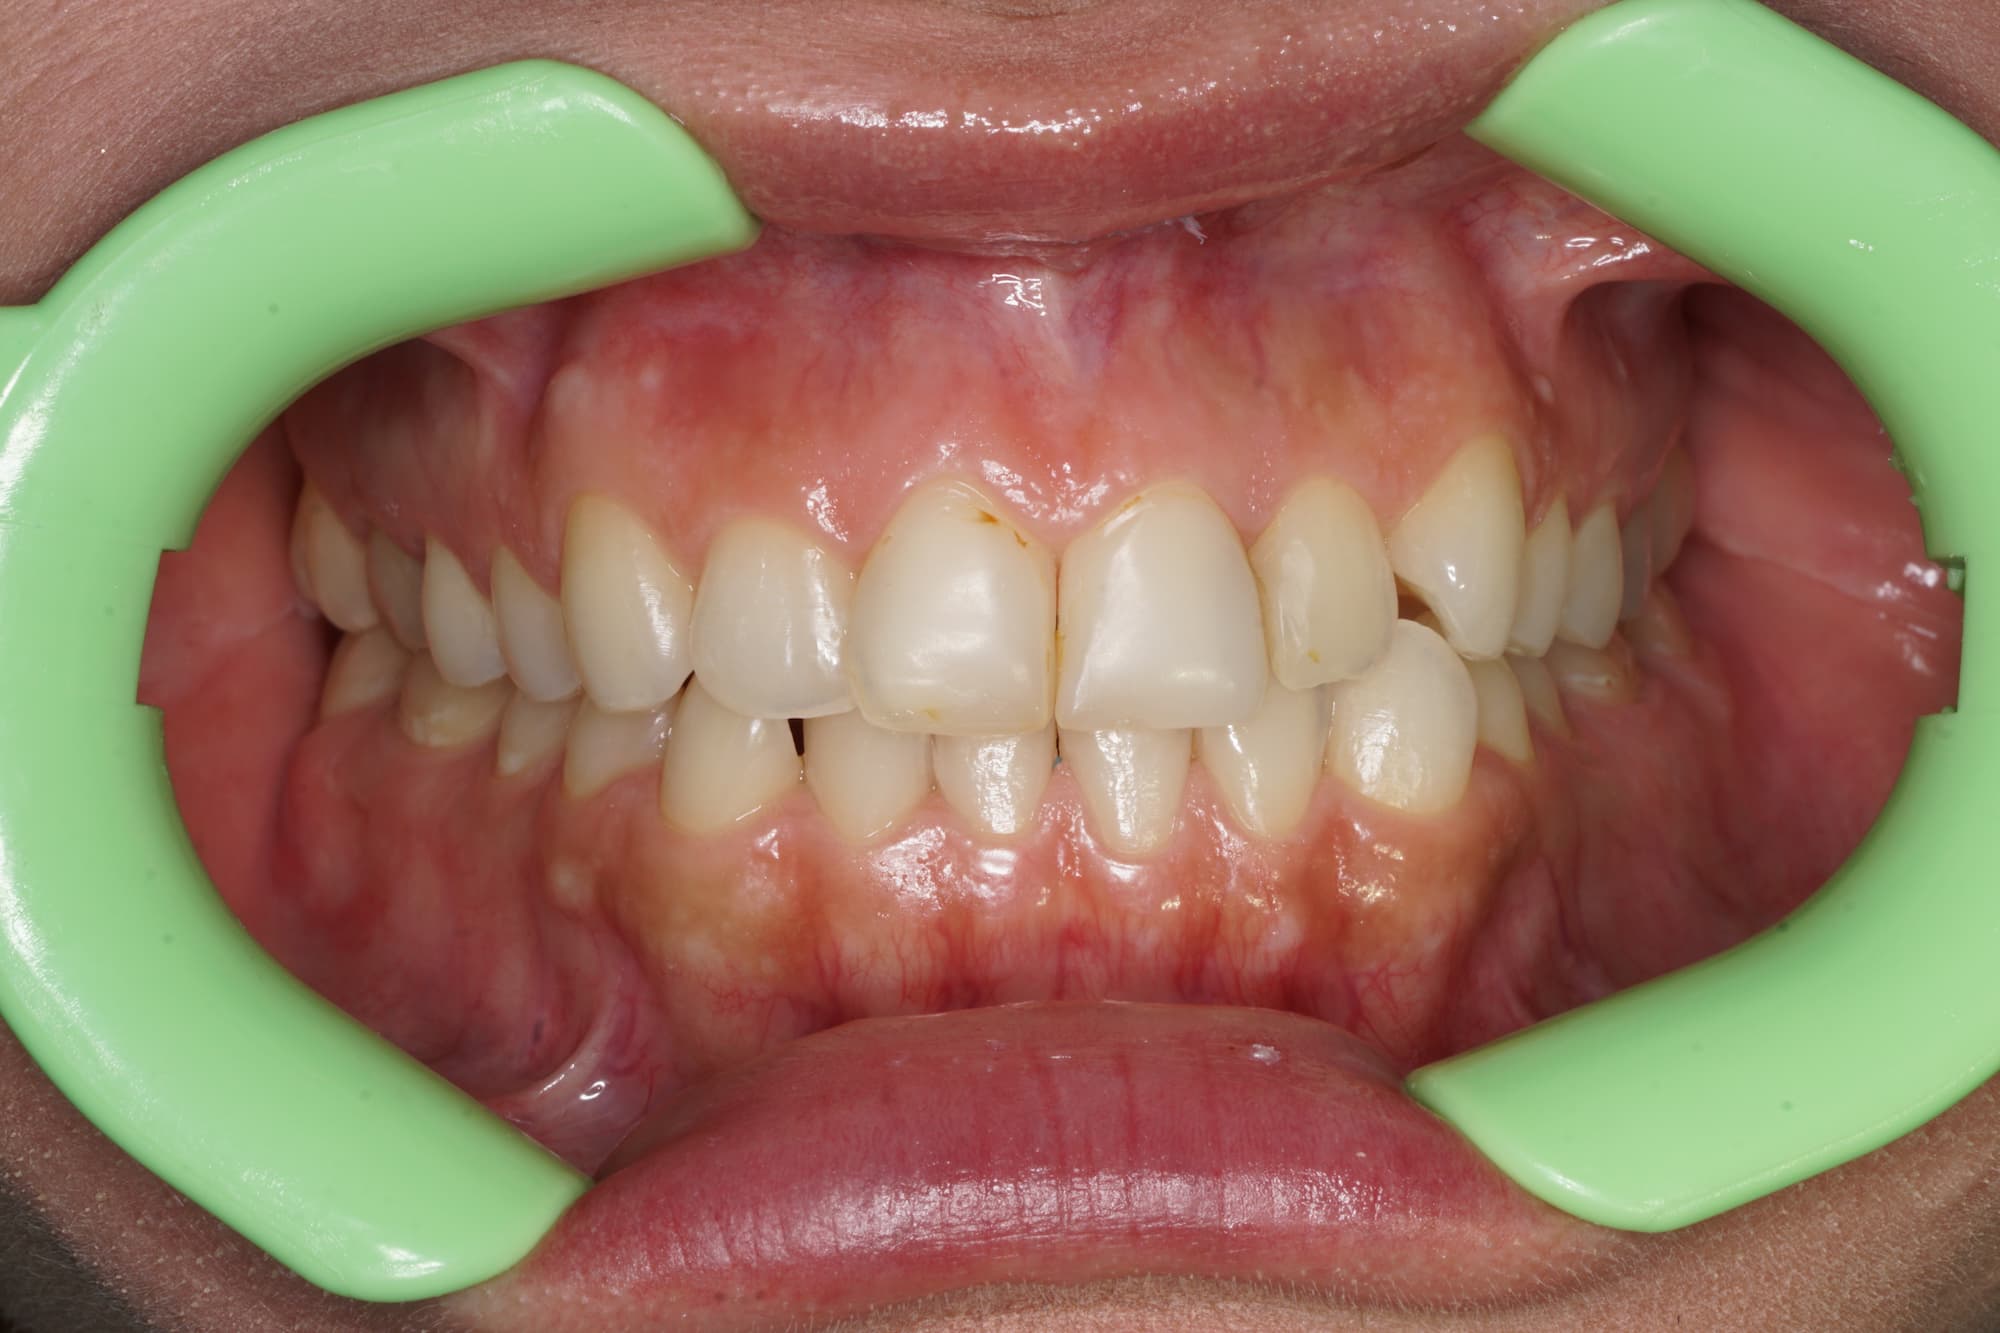

Наши работы